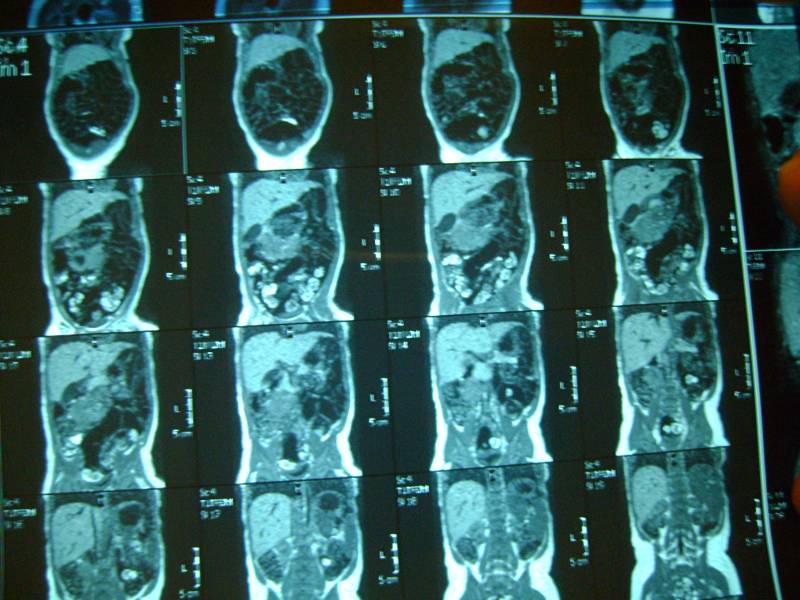

еще